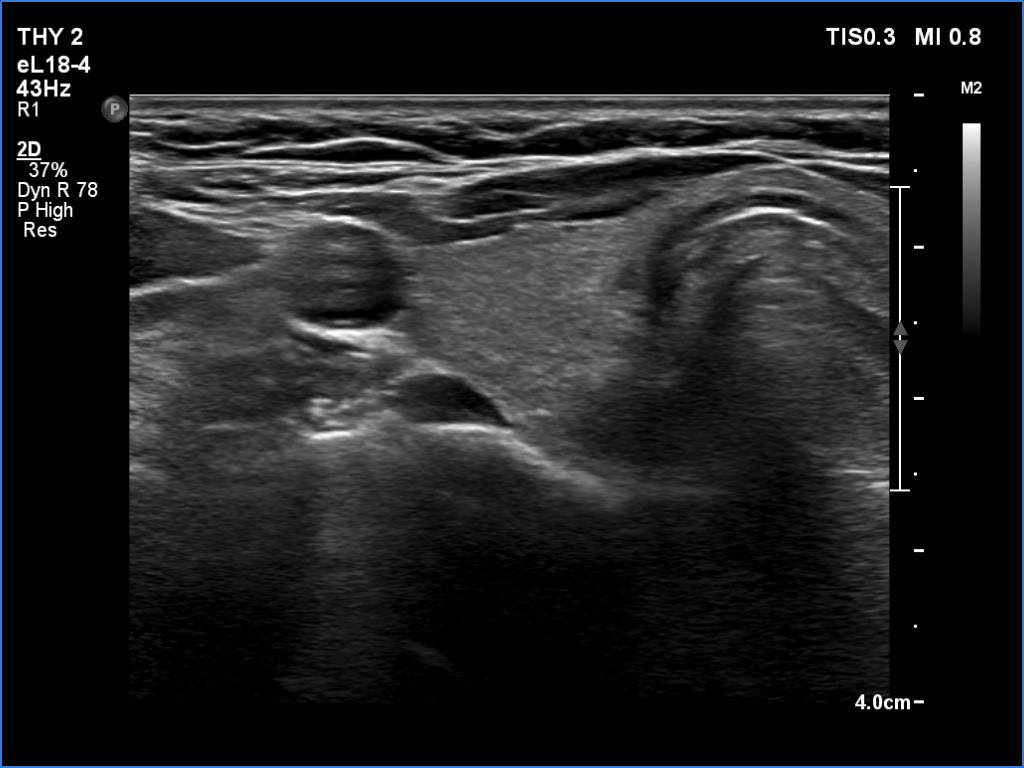

First examination (1st row of images)

Clinical presentation. A 51-year-old woman was referred for aspiration cytology of a thyroid nodule. She was examined because of depression and weight gain. (We met the patient in May 2020 during the COVID epidemic. Her endocrinologist did not meet the patient.)

Palpation: no abnormality.

Ultrasonography. The thyroid was echonormal and had several tiny hypoechoic areas and an echonormal nodule in the lower third of the right lobe. We did not find any lesion of clinical or oncological significance.